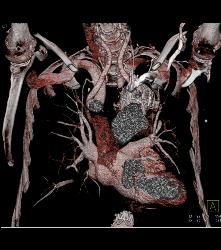

Atherosclerotic Disease Abdominal Aorta